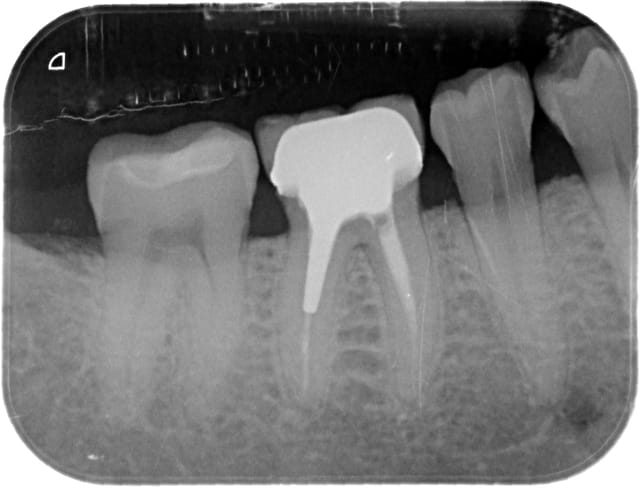

Mon patient se plaint de douleur intermittente au niveau de la 46. pas d'abcès pour l'instant .

Je soupçonne un problème au niveau du plancher.

une douleur intermittente signe en général une pulpite et non pas un problème paro/desmodontal (il y a une légère atteinte de la furcation)

pour moi il doit y avoir un bourrage entre 45 et 46 vu que le point de contact est inexistant. il a mal et quand la bouffe part ça va mieux. Ton plancher est nickel.

il n'y a pas de reprise carieuse au niveau du plancher... Ce plancher n'a rien! Sur cette radio, c'est le niveau osseux qui donne à la dentine susjacente un aspect plus sombre que la dentine sous-jacente... Aucune carie, ni atteinte de la furcation!

Par contre le traitement canalaire m'a l'air insuffisant, et l'on peut distinguer une image radioclaire au niveau des racines M et D...

tout à fait d'accord sur la non atteinte de la furcation d'après la radio mais juste la superposition osseuse.

Pour moi, mais je me trompe peut etre ; il n'y a sans doute rien d'autre qu'un bourrage alimentaire entre 45/46. Ton plancher n'a rien, l'endo est nettement au dessus de la moyenne et les tissus durs adjacents semblent sains. La couronne a ete plutot bien realisee, avec des limites sans debordements, bref, moi, je ne toucherai pas ce truc la ! Encore que si les symptomes sont dus a un bourrage, demonter tout ce bin's va effectivement soulager ! ;-)

ce que j'observe :

-douleur intermittente

-corne pulpaire distale de 46 retractée

-aspect diffus de pulpolithes dans la chambre pulpaire de 47

-canaux mésiaux très fins

et je vais sortir aussi une hypothèse : pulpite chronique sur 47 devenant subaigue